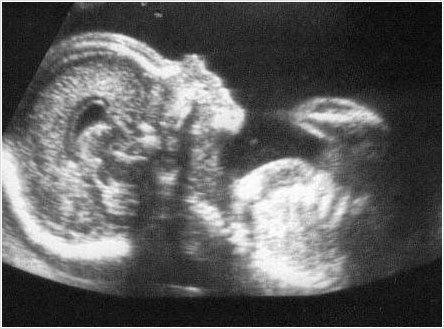

Ecografia 22-24 semanas + Doppler + Cervicometria

Imagen numero 1 del servicio Ecografia 22-24 semanas + Doppler + Cervicometria

-Evaluación anatomía fetal para pesquisa de malformaciones congénitas -Determinar riesgo de parto prematuro espontáneo -Determinar riesgo de insuficiencia placentaria: preeclampsia precoz y restricción de crecimiento fetal